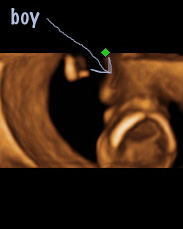

The 3d and 4d image is from looking at the top of "his" head and you can see a leg to either side with something in the middle. She said the 4d part, the head is at the center of the picture and it would be like looking through a tunnel to his boy parts where the arrow is that says boy!

Im not sure if you can zoom in or not but in the 4d image, you can see a "stick" and thats what made her say shes 100% sure. Ive come up with a million other things it could be! haha!

I thought the 4d showed a shot through the skull!! How clever is that:) I would lean boy too if the tech was confident with what she was seeing to say it, shame that nub area is cut off though! Best of luck:luck: